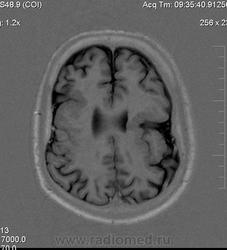

Мужчина 32 лет. Из анамнеза: перинатальное повреждение ЦНС, ДЦП, дизартрия, правосторонний верхний монопарез. С 16 лет приступы эпилепсии.

Аплазия прозрачной перегородки. Шизэнцефалия с открытыми краями в лобно-теменной области слева. Шизэнцефалия с закрытыми краями в лобной области справа? Утолщение коры по контуру расщелин и в области глазничной извилины правой лобной доли. Микрогирия? Гиперостоз костей свода черепа. Уважаемые коллеги, возможно я ошибаюсь, или есть еще аномалия?

Спасибо. Как тогда лучше сформулировать заключение? МР-картина кортикальной дисплазии : двусторнняя шизэнцефалия с утолщением коры по контуру расщелин, микрогирия в лобной области справа, очаг гетеротопии серого вещества в области  глазничной извилины правой лобной доли. Признаки септооптической дисплазии (гипоплазия зрительных нервов, аплазия прозрачной перегородки). Лиссэнцефалии не вижу. Есть сомнения по поводу шизэнцефалии справа (может быть я запуталась в микрогирии и мерещится шизэнцефалия?) Нет ли какой либо анамалии развития черепа?

На мой взгляд, полимикрогирия двусторонняя (конвекситальные отделы дорзальных отделов лобных долей и частично теменных, а также в базальном отделе полюса правой лобной доли) + закрытая шизенцефалия левой лобно-теменной области. Аплазия прозрачной перегородки (как признаки лобарной голопрозенцефалии).